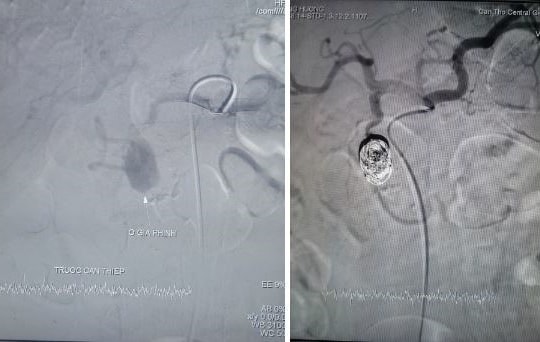

Cứu sống bệnh nhân vỡ giả phình động mạch vị tá tràng hiếm gặp

PLBĐ - Bệnh viện Đa khoa Trung ương (BVĐKTƯ) Cần Thơ vừa can thiệp thành công, cứu sống bệnh nhân xuất huyết tiêu hóa do vỡ ổ giả phình kích thước lớn từ nhánh động mạch vị tá tràng, bằng phương pháp can thiệp nội mạch.